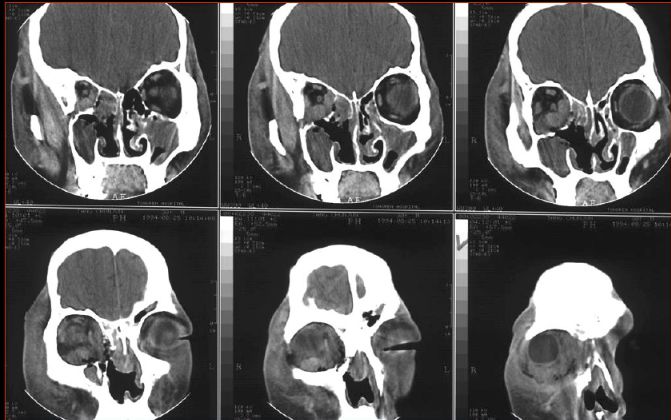

急性鼻窦炎

筛窦异物伴急性感染